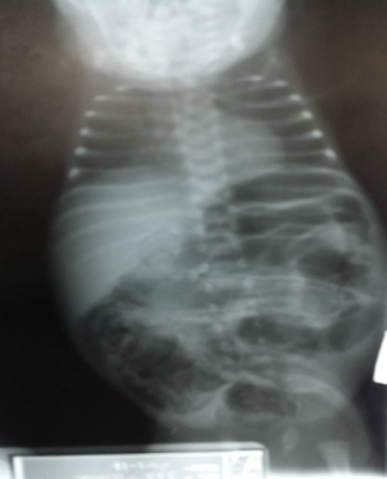

Case 25: Diaphragmatic Hernia

Case Study

Questions

- A- most important test

- ABG

- B- what is the diagnosis?

- Congenital diaphragmatic hernia

- C- what is the definitive treatment?

- Surgery

- D- give one association

- Lung hypoplasia

DIAPHRAGMATIC HERNIA:

- A newborn with left congenital diaphragmatic hernia. Note the scaphoid abdomen and the barrel-shaped chest.

Full-term baby normal vaginal delivery

- Shows severe respiratory distress. Air entry impaired in the left side, and heart apex heard in the right side.

- What is the cause of this respiratory distress? Left side massive diaphragmatic hernia.

- Treatment: Surgical repair